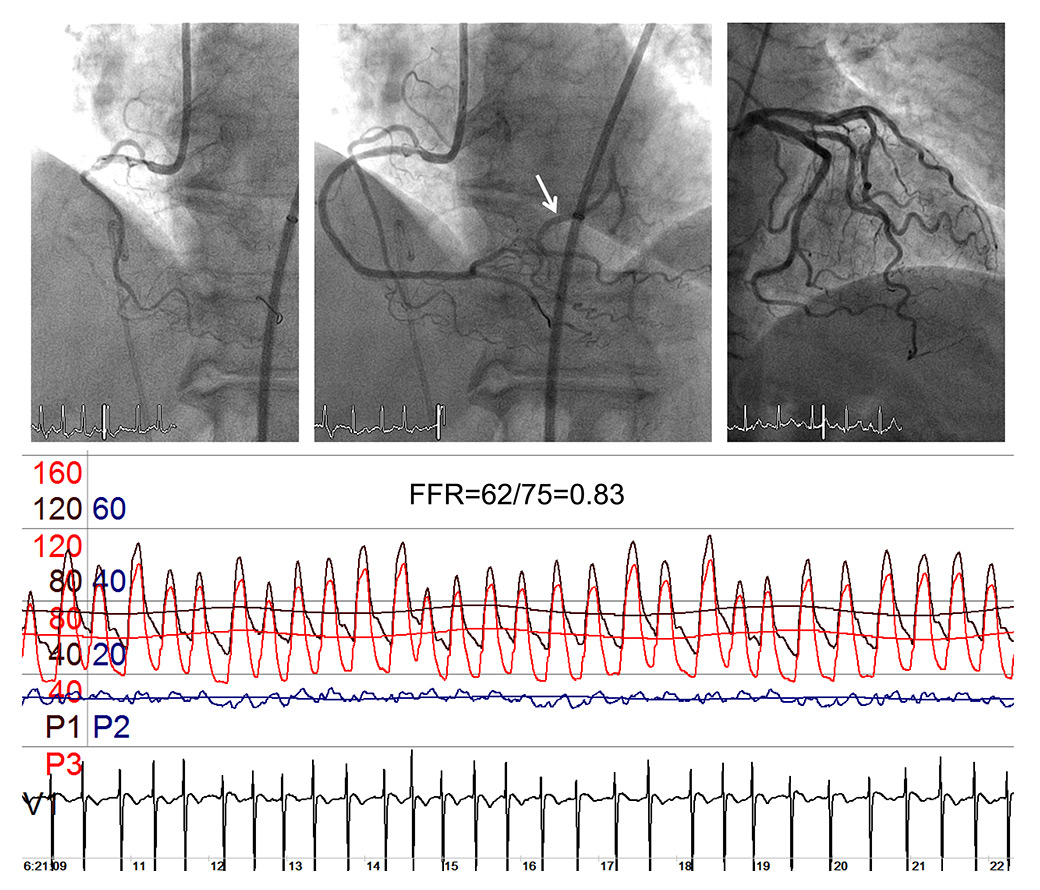

Whereas in patients with acute coronary syndrome the beneficial effect on outcomes of percutaneous coronary intervention (PCI) is undisputed [1], PCI in chronic stable coronary artery disease (CAD) has not been demonstrated to reduce the incidence of myocardial infarction or death [2, 3]. In a very recent meta-analysis including more than 93,000 patients [4], it has, however, been concluded that there may be “evidence for improved survival with new generation drug eluting stents but no other percutaneous revascularisation technology compared with medical treatment”. There is, at present, even more evidence that the outcome from PCI is dependent on the amount of myocardial ischaemia [5, 6]. In this context and because only a minority of patients with stable CAD undergo noninvasive stress testing for ischaemia detection prior to elective PCI, an array of invasive coronary haemodynamic measurements for functional stenosis severity assessment has been developed [7]. Owing to the technical robustness of coronary pressure measurements, pressure-derived haemodynamic parameters are employed more frequently than coronary flow velocity or temporal flow parameters. At present, the most often used invasive coronary haemodynamic parameter is pressure-derived fractional flow reserve (FFR), which is calculated as the ratio of mean, i.e., time-averaged, coronary pressure obtained distal to one or more stenotic lesions of interest (Pd in mm Hg) divided by the simultaneous mean aortic pressure (Pao in mm Hg) during hyperaemia (fig. 1) [8]. An FFR ≤0.80 as described by the authors of the most recently published study on the topic is “a drop in maximal blood flow of 20% or more caused by stenosis” [9]. The open-label FFR vs Angiography for Multivessel Evaluation 2 (FAME2) trial randomly allocated patients with clinically overt chronic CAD and FFR ≤0.80 to PCI plus medical therapy or to medical therapy alone [9]. The rate of the composite of death from any cause, myocardial infarction, or urgent revascularisation within 2 years was 8.1% in the PCI group and 19.5% in the medical therapy group (p <0.0001). Not entirely surprisingly, this reduction in adverse events was driven by a higher rate of urgent revascularisation in the medical group.

Figure 1

Angiogram of the left coronary artery with serial stenoses of the left circumflex artery (upper panels). The pressure sensor wire (location of the sensor at the end of the opaque tip) is first positioned proximal to the tightest stenosis (left upper panel), and then distal to it (right upper panel). The pressure tracings (lower panel) are recorded with the pressure sensor distal to the stenoses (wire tip in the marginal branch). The following phasic and mean pressures are recorded simultaneously: Aortic pressure, Pao (mean) in red, coronary pressure distal to the stenoses in black (Pd), central venous pressure in blue (CVP). Fractional flow reserve (FFR) is taken as the steady state minimum ratio of Pd/Pao (broken lines) over several cardiac cycles.